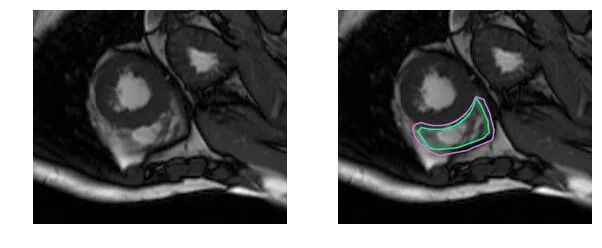

下面用几组图片来感受一下这种分割问题的困难。下图是右心室的MRI图片:

这些区域由于本身的特性,其难易程度和分割手段也存在不同。通常来讲,普适性的心脏分割算法能够实现基本的区域分割,但是要实现精准分割还是需要对单独区域进行单独处理。相对而言,右心室(RV)的分割难度更大,我们就以此为例分析一下其存在的难点。

心脏分割问题中,每个区域的形态、工作方式不同,从而导致了每个区域的分割方法和难点也不同。以右心室为例,其存在的难点有:

右心室新月形形状复杂,从基部到顶点一直变化

简单来讲,左心室是一个厚壁的圆柱形区域,而右心室是一个不规则形状的物体,较薄的心室壁有时会与周围的组织混在一起。